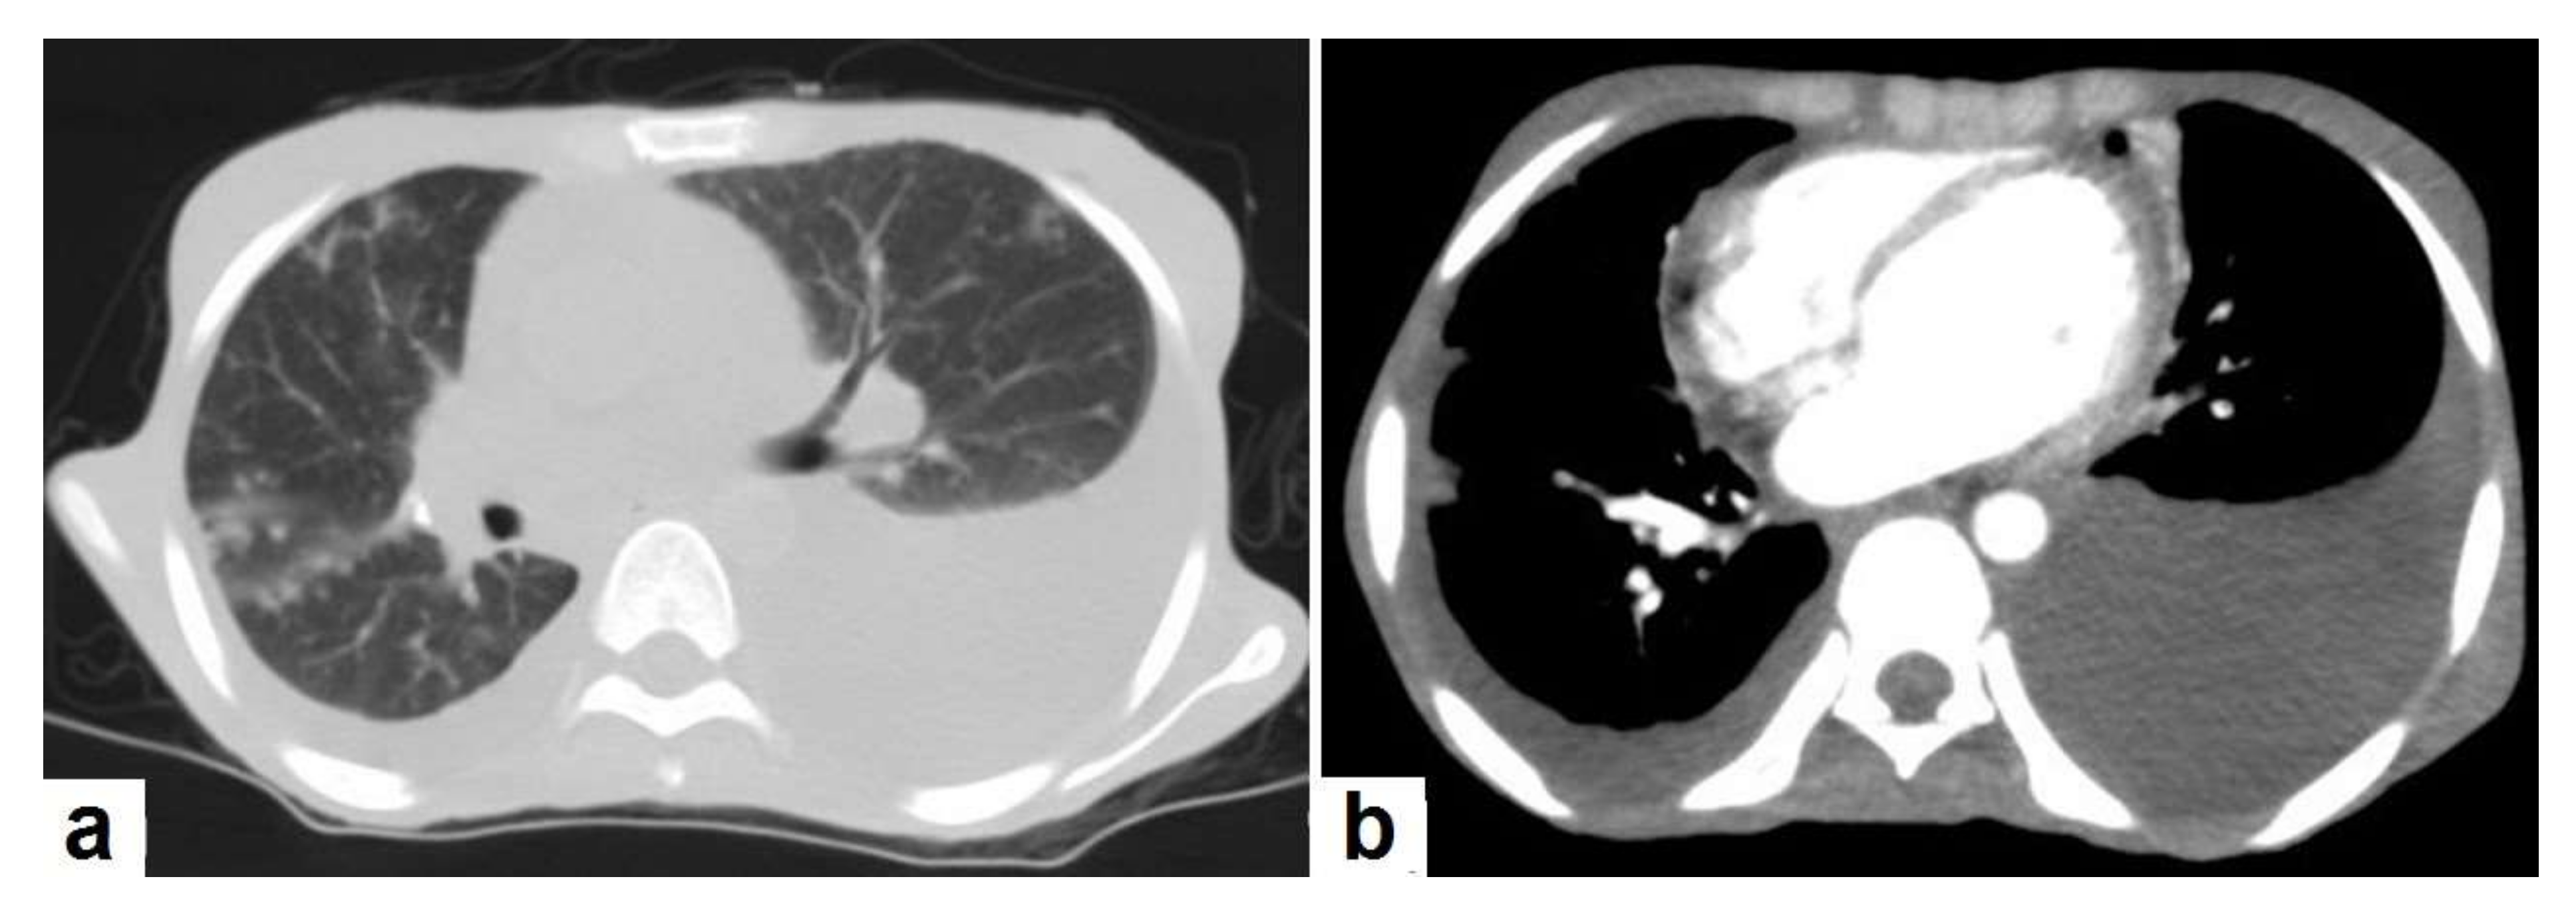

2.1. Pulmonary TB

Lungs are the most common organ affected and they are often the initial sites of TB infection [11]. Pulmonary TB can be divided into primary and postprimary (reactivation), each with appropriate radiological features that are overlap considerably. It can involve the lung and extrapulmonary organs in the chest, such as pleura or lymph nodes [12,13].

• Consolidation (Figure 3) is considered to be one of the most common features of postprimary TB, which is usually focal, patchy heterogeneous, or poorly defined. It involves the apical and posterior segments of the upper lobes and the upper segments of the lower lobes [10]. Consolidation with ipsilateral enlarged hilar or paratracheal LNs could strongly suggest TB. CT is better able to detect small and subtle TB consolidations, which are usually peribronchial or subpleural and involve multiple lung segments [13].

• Cavitation (Figure 3 and Figure 4) is a common finding in postprimary TB, and it is characterized as being several centimeters in size with thick irregular walls. Cavities are often seen within consolidation and may persist after treatment predisposing to a bacterial or fungal superinfection or adjacent vascular erosion causing hemoptysis [1,10]. In postprimary TB, both consolidation and cavitation have a predilection for the apical and posterior segments of the upper lobes and the upper segments of the lower lobes [1,14]. This predilection of TB is attributed to the relative over-ventilation, high oxygen tension, and delayed lymphatic clearance in these regions [16]. Thick wall cavities are an important differential diagnosis of a pulmonary abscess, septic emboli, aspergilloma, granulomatosis with polyangitis (Wegener’s granulomatosis), lung malignancy, and others [17].

Figure 3. Post primary TB in a 45-year-old male with cough and hemoptysis. Axial images of chest CT show (a) cavitary lesions in the right upper lobe and upper segment of the left lower lobe surrounded with consolidation, (b) cavitary lesion in the upper segment of the left lower lobe with thick irregular wall surrounded by patchy ground glass opacities, (c) centrilobular nodules and tree-in-bud nodules, and (d) consolidation in the left lower lobe with air-bronchograms.